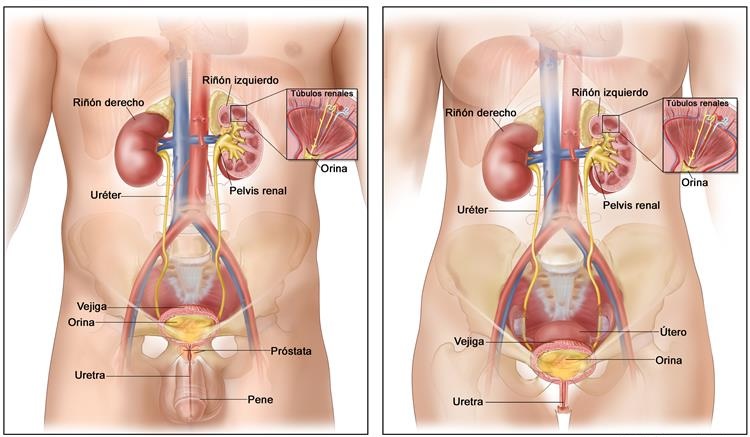

La uretromeatotomía es un procedimiento quirúrgico ambulatorio que se realiza para ampliar el meato uretral y el segmento distal de la uretra cuando existe una estrechez que dificulta la salida normal de la orina 🚻

Es una intervención frecuente en casos de estenosis del meato o estenosis uretral distal.

Códigos de Exámenes y Procedimientos Ambulatorios Asociados a su Búsqueda:

- 1902061: Uretromeatotomía.

- 1902070: Meatotomía.

- 1902071: Meatoplastía.

- 1902056: Dilatación uretral instrumental.

- 1902057: Uretrotomía interna endoscópica.

- 1902062: Uretrocistoscopía.

- 1902074: Uretroplastia.

- 1902069: Revisión de meatotomía con reparación.